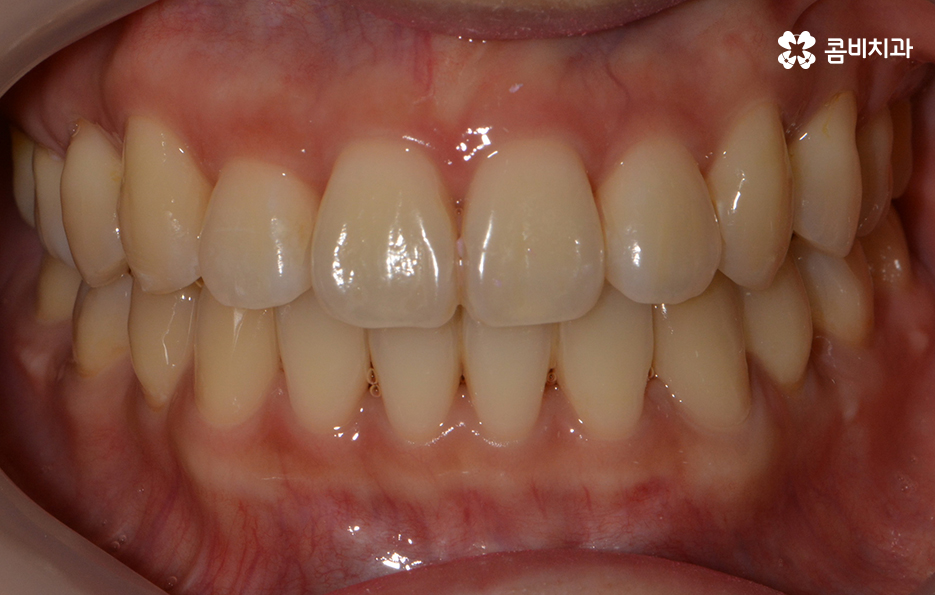

돌출된 앞니로 인해서 교정을 원하신 상황이며 치료 전 치아 상태

치열의 상태가 정면으로 바라봤을 때 비교적 가지런한 편이지만

측면으로 볼 때 유독 앞으로 돌출된 경우라면

입모양과 얼굴형에도 영향을 주기 때문에

앞니치아교정을 알아보시는 분들 중에서

이러한 고민으로 인해 치료를 원하시는 경우가 많습니다.

치료가 시작되기 전 치아 상태

돌출치아로 인한 돌출입이나 앞니의 벌어짐이 비교적 심하지